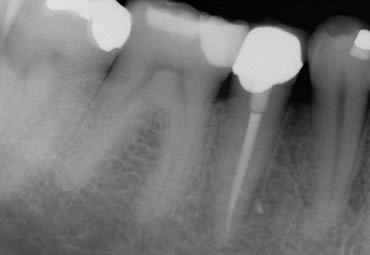

Large Perio-endo lesion, before treatment, during treatment and at 18 month follow up